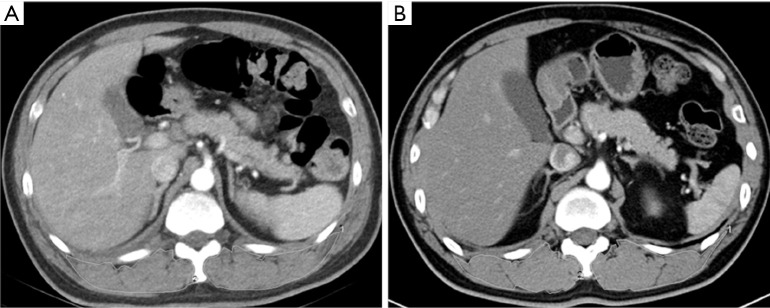

Figure 1.

Representative single-slice chest CT images. Two PD-L1 positive (A) and negative (B) patients were used to calculate SMA and SMD, respectively. Using computer software to measure the SMA and SMD of manually sketched areas (white line). CT, computed tomography; PD-L1, programmed cell death-ligand 1; SMA, skeletal muscle cross-sectional area; SMD, skeletal muscle density.